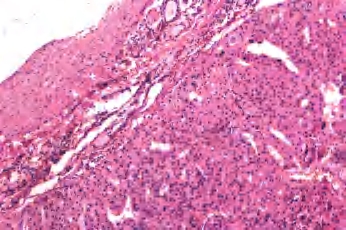

(1)嗜酸细胞腺瘤 单发,界限清楚,包膜完整,具有特征性的红褐色外观,常见中央区瘢痕形成。构成肿瘤的细胞有富含颗粒的嗜酸性胞浆,核大和明显的核仁,胶质常浓染并可形成类似沙砾体的结构,局部可见到乳头结构(图3-32至图3-34)。

图3-32 嗜酸性细胞腺瘤